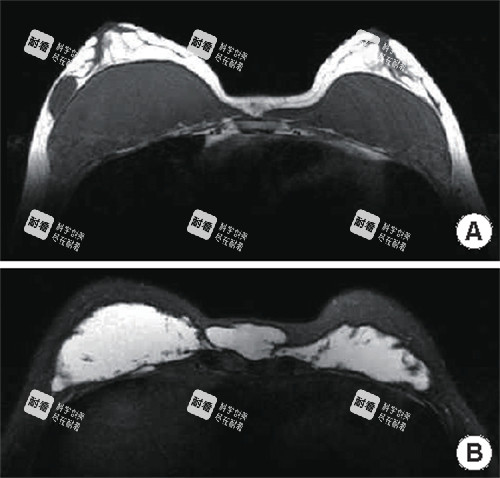

精密可视化操作:采用靠前的 “3D内窥镜结合超声引导” 技术。内窥镜能将手术视野高清放大,让医生在屏幕上清晰分辨奥美定与正常组织;超声则能精密定位深层、隐匿的注射物,实现“指哪打哪”的精密清除。

分层清奥与组织保护:技术核心在于 “分层取出” 。奥美定在体内常呈“树根状”或“蜂窝状”扩散,杨医生通过精细操作,逐层分离、剥离,在较高的效率清除异物的同时,较大程度地保护了血管、神经及健康的乳腺组织与脂肪组织。

术前精密检查:高分辨率MRI(磁共振)检查,这是精密判断奥美定分布范围、层次与毗邻关系的金标准。